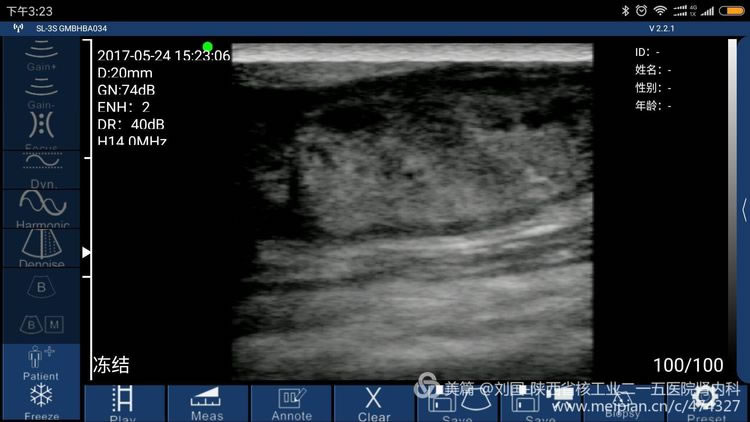

索诺星无线超声所查的结果,显示器是我的小米max。

索诺星无线超声检查的头静脉情况,显示器是我的小米max。